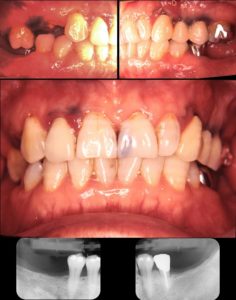

2001.6 初診時 59歳

初診時

59歳女性

主訴

奥歯でうまく噛めない

患者さんは久しぶりの歯科受診で口の中は長い間放置されていました。下の奥歯が無いため、上の奥歯は動いてしまっています。しっかり歯に合っていない被せ物があり、虫歯も多く認めました。